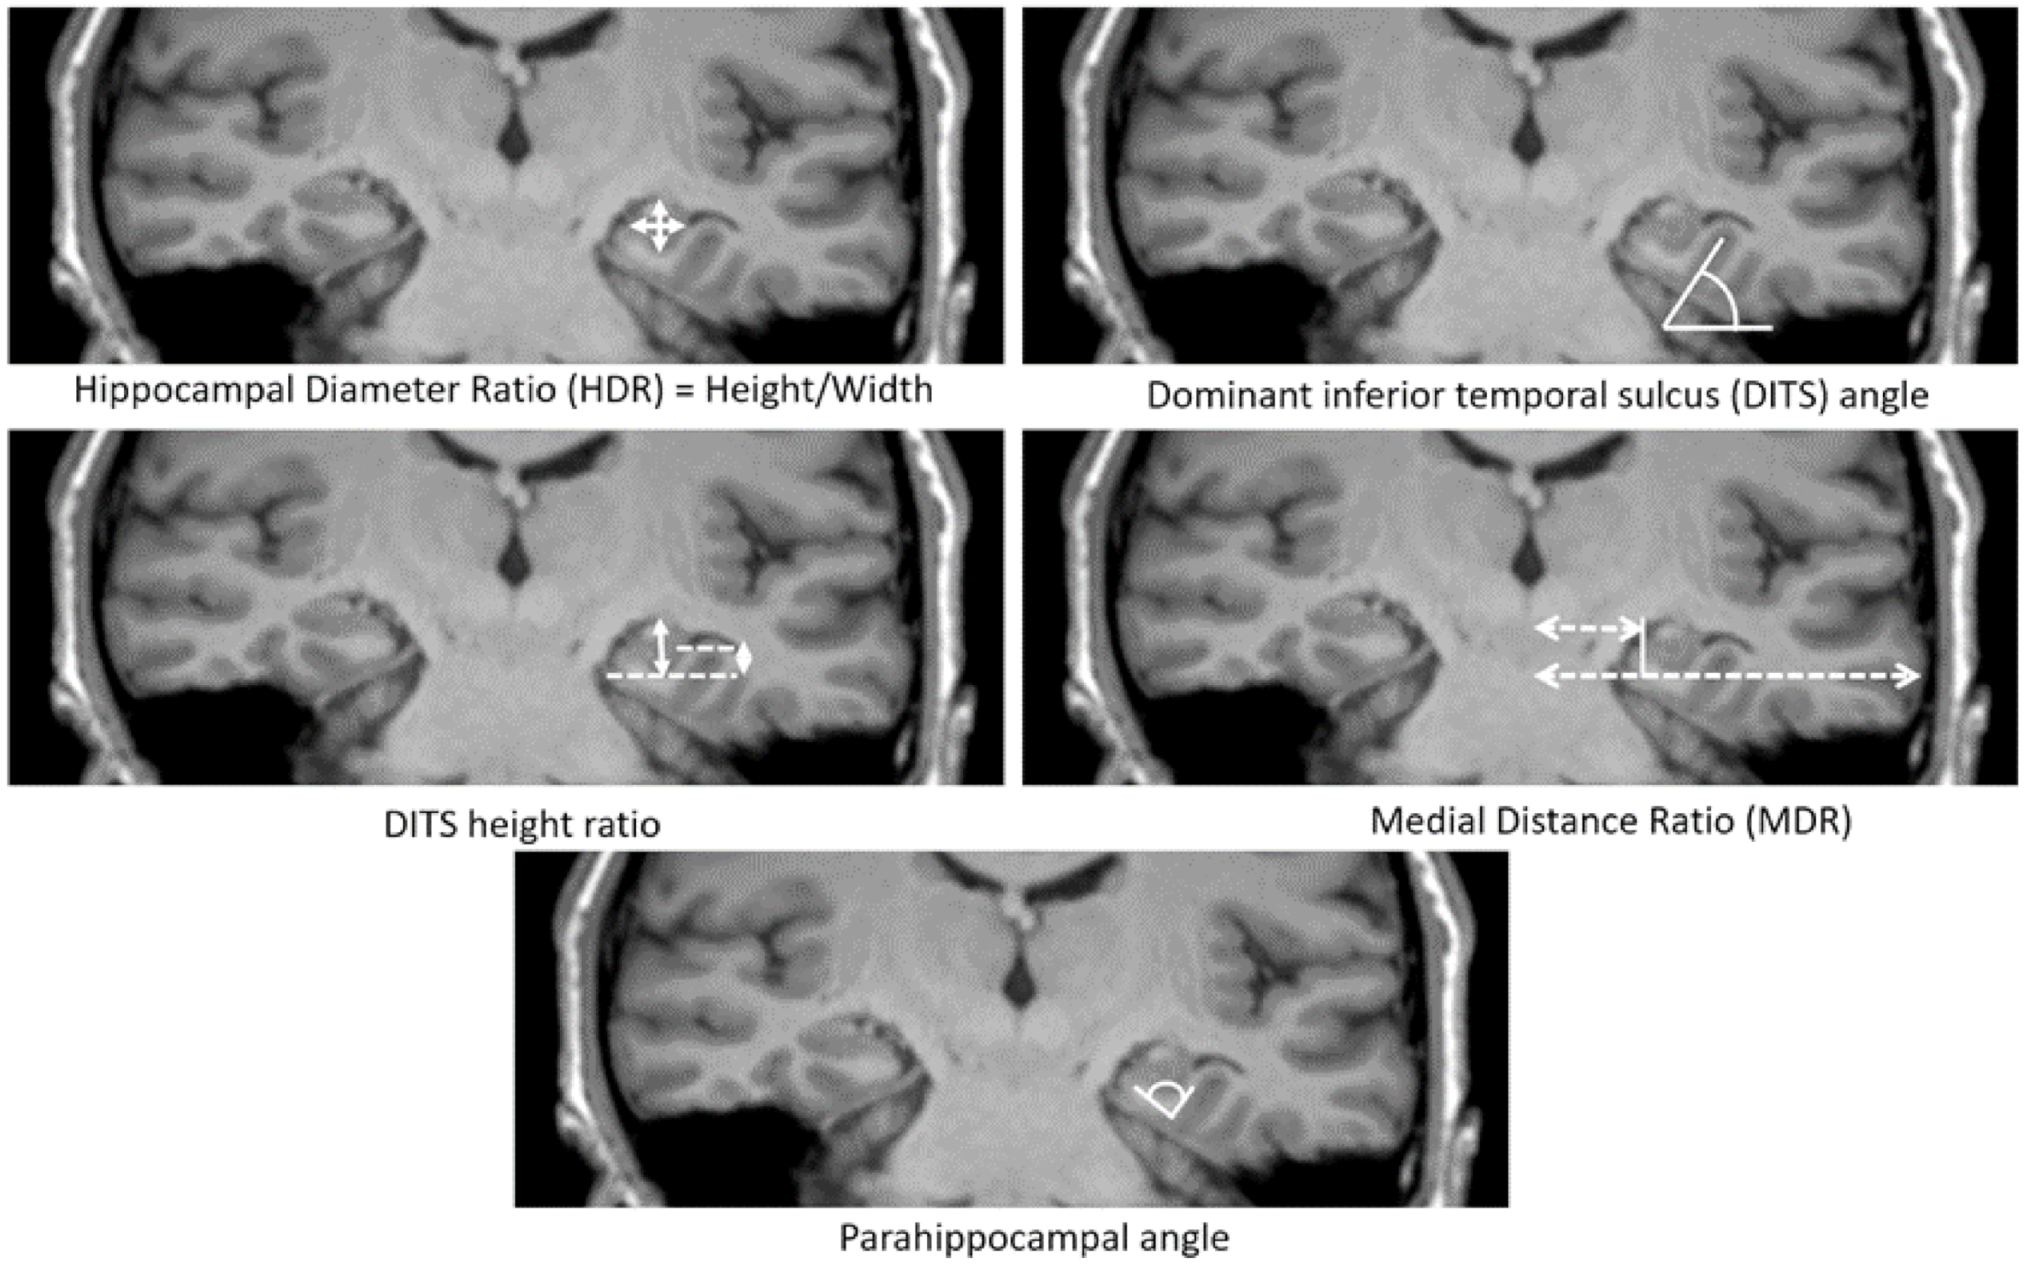

6. Measurements of HIMAL